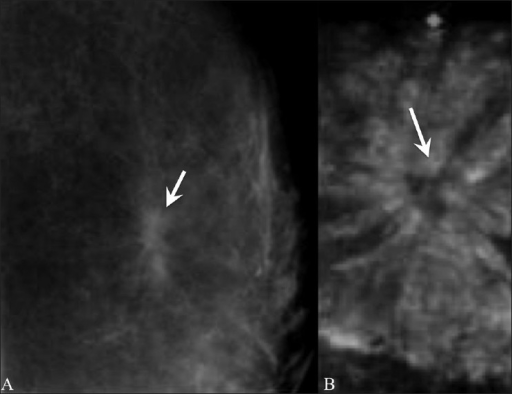

Radial Scar

Radial scars (complex sclerosing lesions) are hardened areas of breast tissue surrounded by abnormal ducts and tissue structures. Most radial scars are found on mammograms. As they resemble cancer, they require core biopsy for testing. Surgical excision is often recommended to confirm the surrounding tissue is normal. A referral to a breast surgeon is required for further investigation.

Pictorial essay: Breast USG by G. Shah and B. Jankharia is licensed under CC BY 2.0